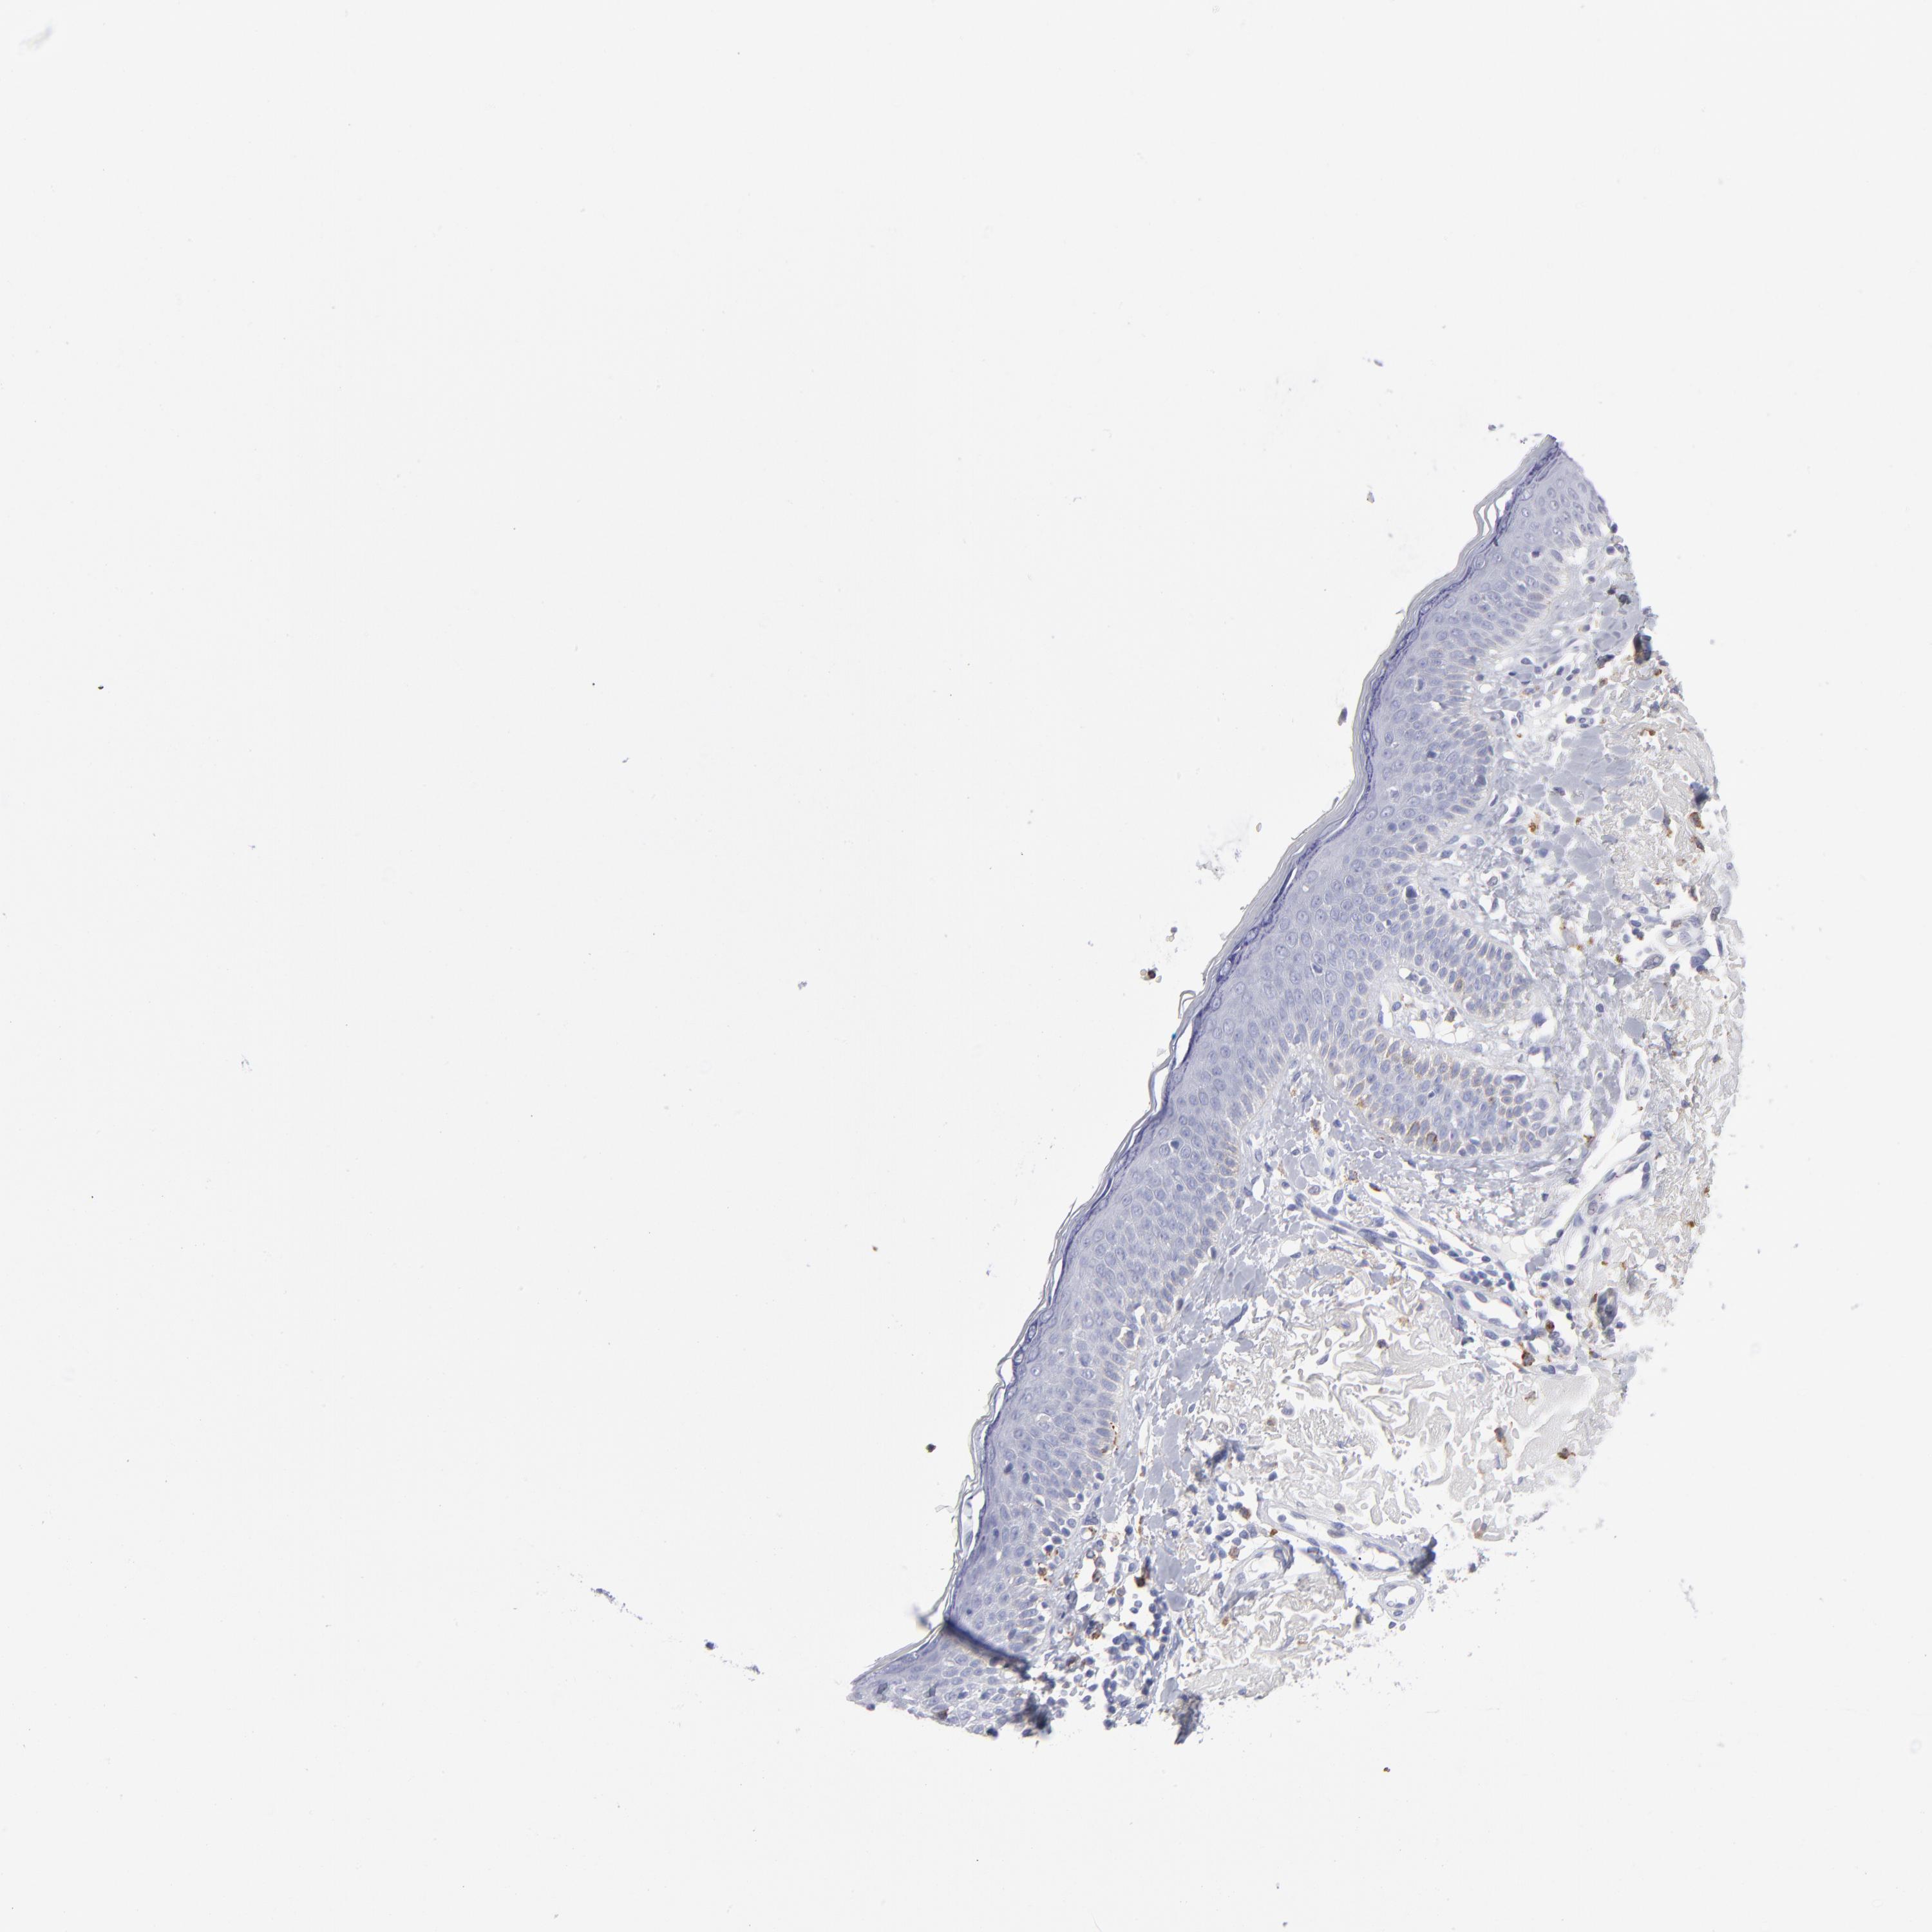

SKIN CANCER - Protein expressioni

A mouse-over function shows sample information and annotation data. Click on an image to view it in a full screen mode. Samples can be filtered based on level of antibody staining by selecting one or several of the following categories: high, medium, low and not detected. The assay and annotation is described here.

Antibody stainingi

Antibody staining in the annotated cell types in the current human tissue is reported as not detected, low, medium, or high, based on conventional immunohistochemistry profiling in selected tissues. This score is based on the combination of the staining intensity and fraction of stained cells.

Each image is clickable and will lead to virtual microscopy that enables deeper exploration of all samples and also displays staining intensity scores, fraction scores and subcellular localization as well as patient and tissue information for each sample.

Antibody HPA003740

Squamous cell carcinoma, NOS